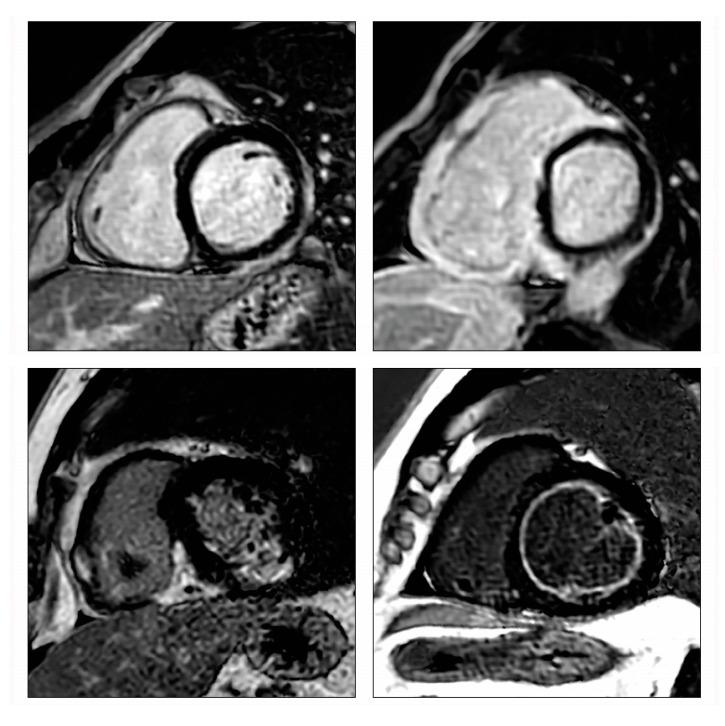

Myocarditis is a disease caused by cardiac inflammation that can progress to dilated cardiomyopathy, heart failure, and eventually death. Several etiologies, including autoimmune, drug-induced, and infectious, lead to inflammation, which causes damage to the myocardium, followed by remodeling and fibrosis. Although there has been an increasing understanding of pathophysiology, early and accurate diagnosis, and effective treatment remain challenging due to the high heterogeneity. As a result, many patients have poor prognosis, with those surviving at risk of long-term sequelae. Current diagnostic methods, including imaging and endomyocardial biopsy, are, at times, expensive, invasive, and not always performed early enough to affect disease progression. Therefore, the identification of accurate, cost-effective, and prognostically informative biomarkers is critical for screening and treatment. The review then focuses on the biomarkers currently associated with these conditions, which have been extensively studied via blood tests and imaging techniques. The information within this review was retrieved through extensive literature research conducted on major publicly accessible databases and has been collated and revised by an international panel of experts. The biomarkers discussed in the article have shown great promise in clinical research studies and provide clinicians with essential tools for early diagnosis and improved outcomes.

心肌炎是一种由心脏炎症引起的疾病,可进展为扩张型心肌病、心力衰竭,并最终导致死亡。包括自身免疫性、药物性和感染性在内的多种病因会引发炎症,炎症会对心肌造成损害,随后出现重塑和纤维化。尽管对病理生理学的认识不断增加,但由于高度异质性,早期准确诊断和有效治疗仍然具有挑战性。因此,许多患者预后较差,幸存者有长期后遗症的风险。目前的诊断方法,包括影像学检查和心内膜心肌活检,有时费用高昂、具有侵入性,而且并不总是能尽早进行以影响疾病进展。因此,识别准确、具有成本效益且能提供预后信息的生物标志物对于筛查和治疗至关重要。本综述随后聚焦于目前与这些病症相关的生物标志物,这些生物标志物已通过血液检测和成像技术进行了广泛研究。本综述中的信息是通过对主要公共可访问数据库进行广泛的文献研究检索到的,并由一个国际专家小组进行了整理和修订。文章中讨论的生物标志物在临床研究中已显示出巨大潜力,并为临床医生提供了早期诊断和改善治疗结果的重要工具。